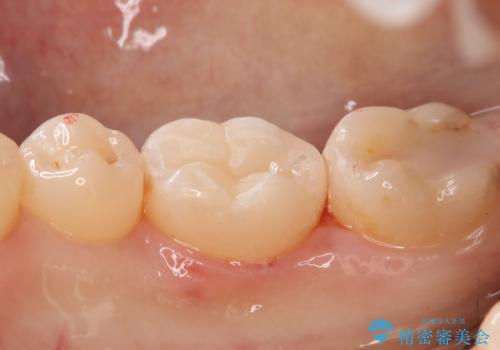

- 右下大臼歯の保険材料劣化に伴う虫歯の治療を希望された患者さまです。

審美性や精度の高い治療を希望されたので切削量や形態を考慮し、セラミックインレーでの治療を選択しました。

保険治療で使用される材料は劣化しやすく直下で虫歯が進行していることが多いです。

今回の患者さまは遠心部の虫歯が深かったのでCRで裏層した上で形成・印象を行いインレーセットを行っています。